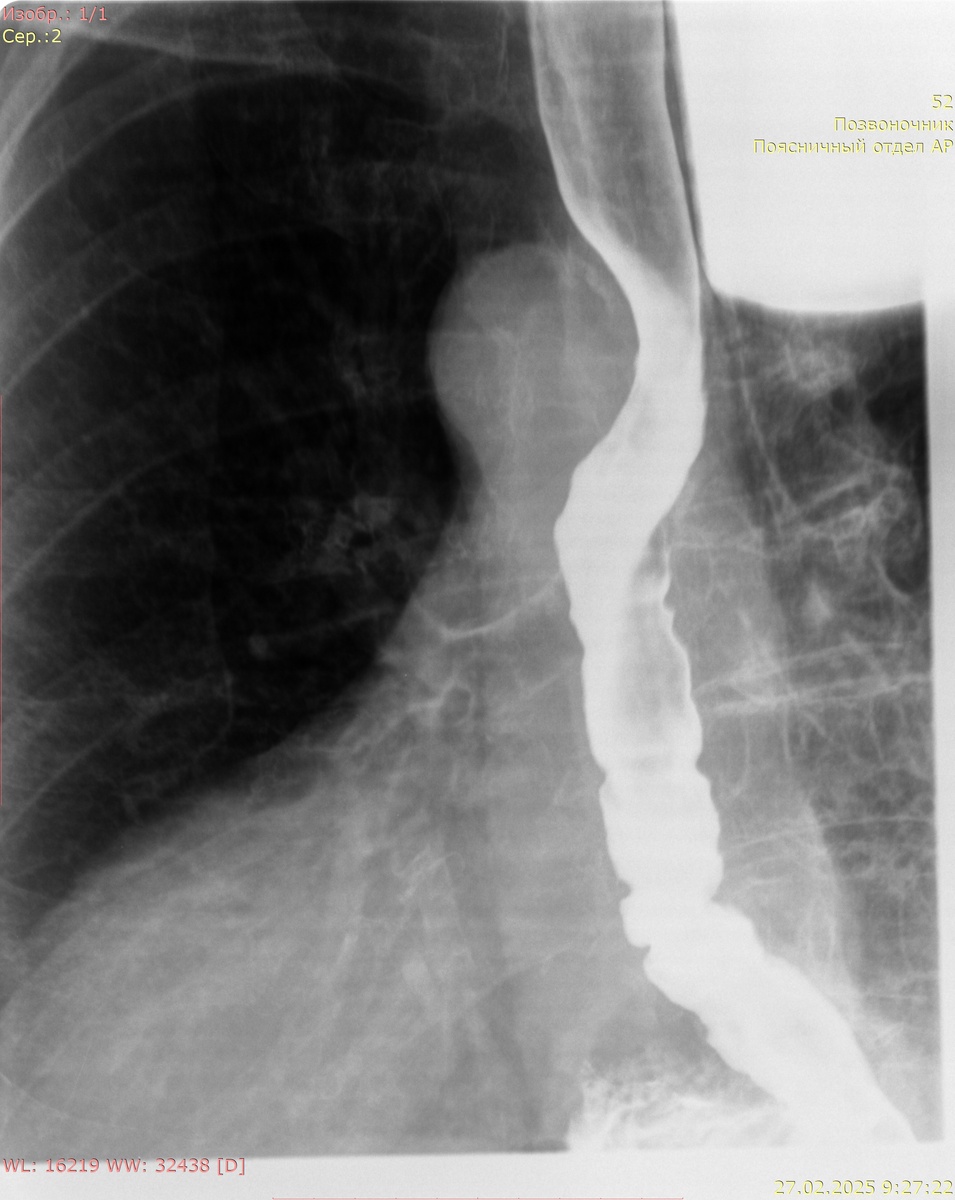

Рентгенография желудка с сульфатом Ва:

Кардиальный жом функционирует. Желудок не деформирован, объем обычный, смещаемость не нарушена. Контуры желудка ровные, отвесные, участков деформации не выявлено. Рельеф слизистой не изменен, складки не утолщены. Контраст своевременно поступает в ДПК. В положении стоя и лежа без натуживания определяется пролабирование кардиальных складок выше диафрагмы размерами 99 мм х 80 мм.

Заключение: картина фиксированной грыжи пищеводного отверстия диафрагмы 4 ст.